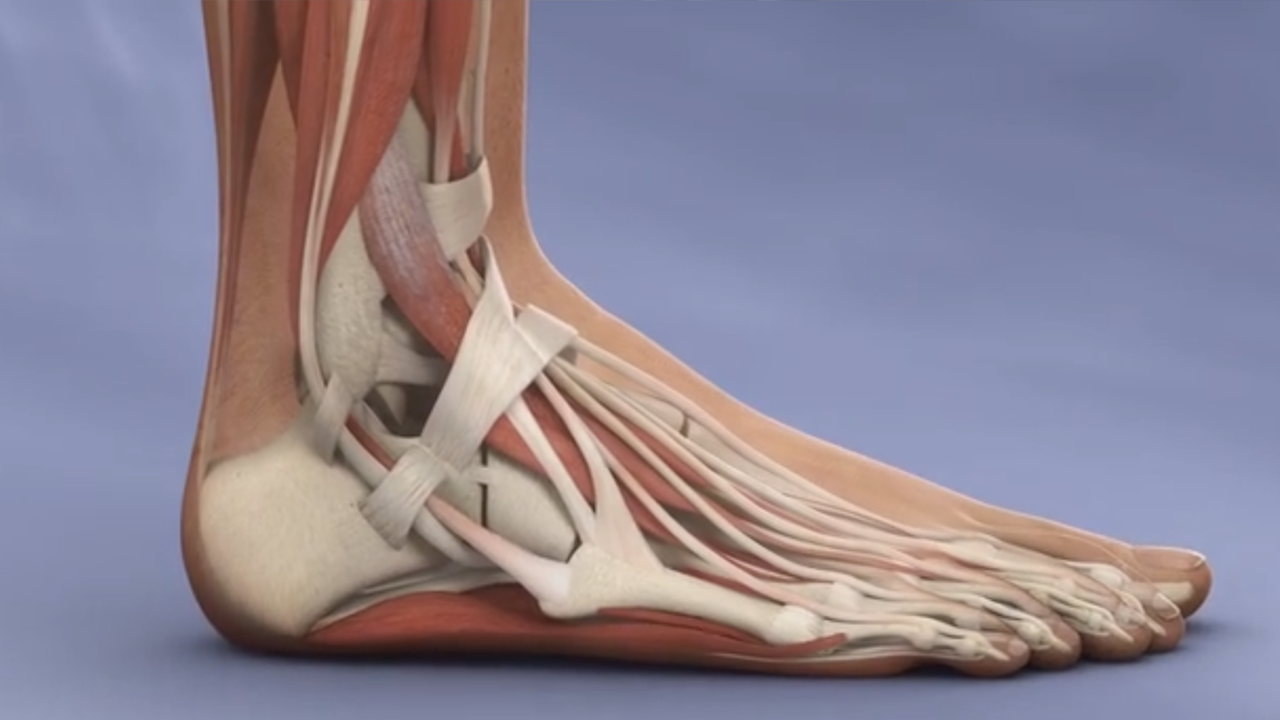

Diagnostic

Diagnostic Ankle Arthroscopy can evaluate the ankle and provide a detailed diagnosis. Ankle arthroscopy allows the orthopaedic surgeon to see the current status of the ligaments, cartilage, synovia and bones forming the complex ankle joint.

Cartilage

Arthroscopic techniques are used to restore damaged ankle cartilage.